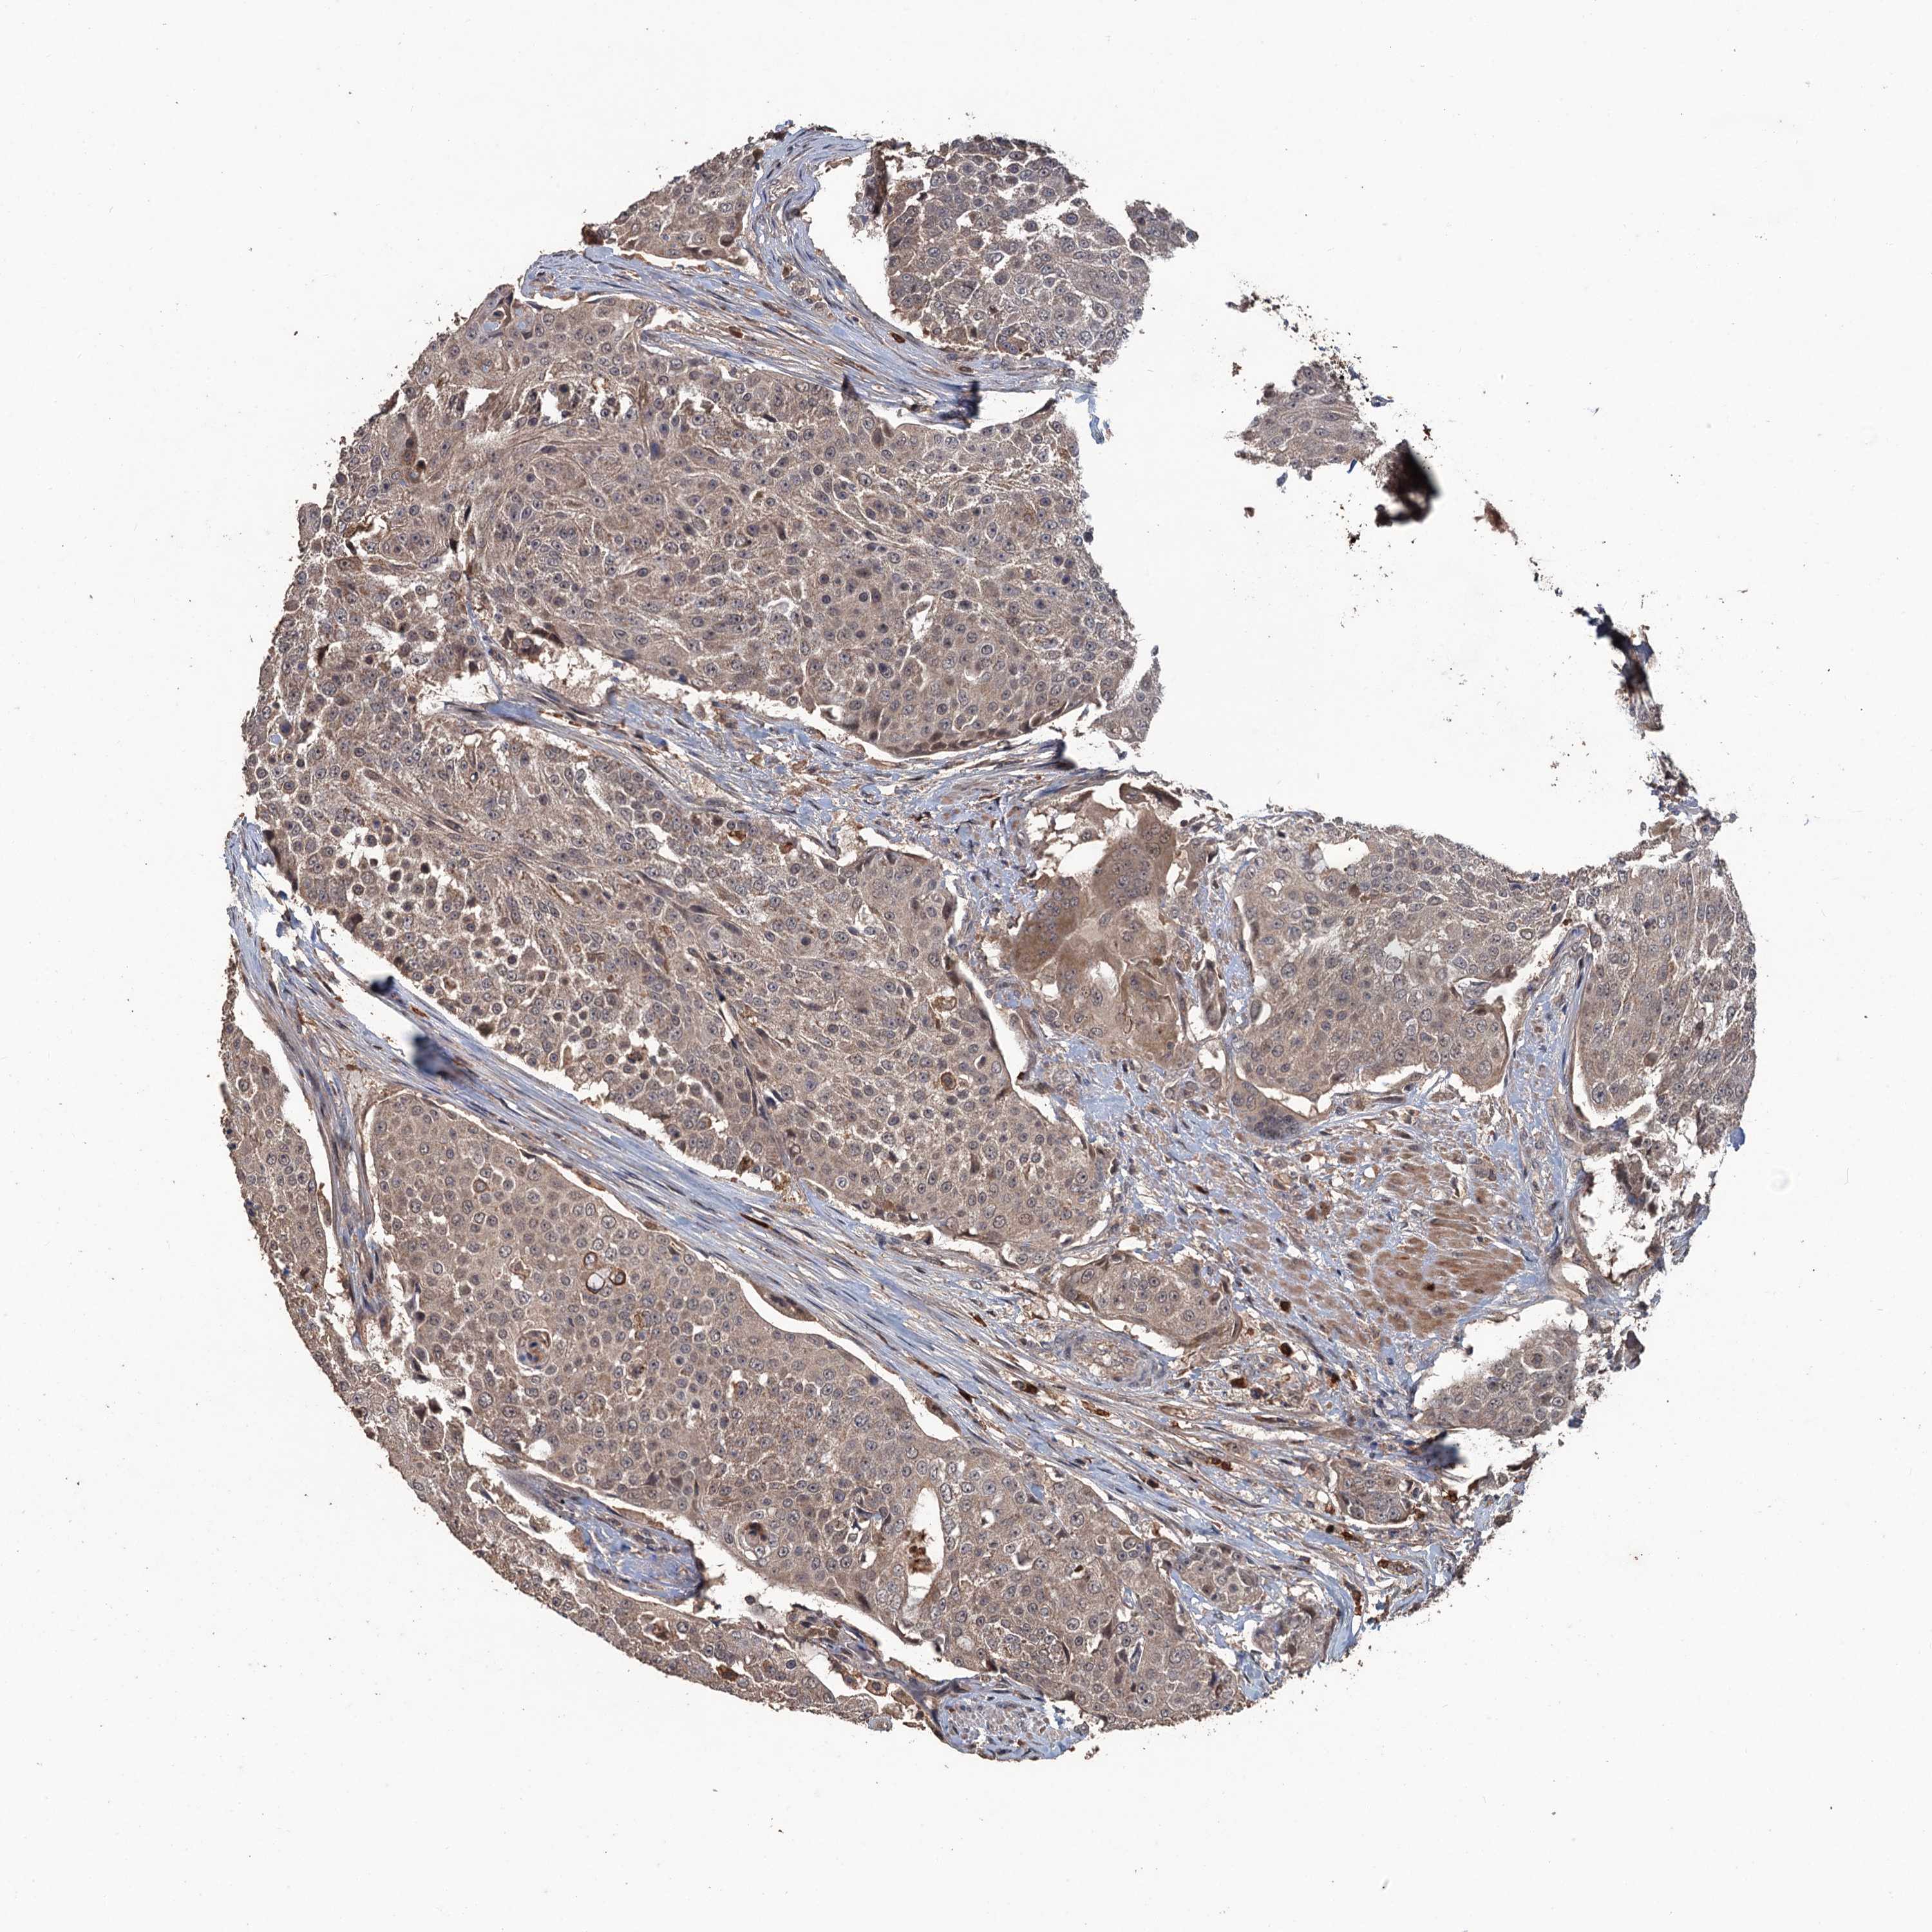

UROTHELIAL CANCER - Protein expressioni

A mouse-over function shows sample information and annotation data. Click on an image to view it in a full screen mode. Samples can be filtered based on level of antibody staining by selecting one or several of the following categories: high, medium, low and not detected. The assay and annotation is described here.

Note that samples used for immunohistochemistry by the Human Protein Atlas do not correspond to samples in the TCGA dataset.

Antibody stainingi

Antibody staining in the annotated cell types in the current human tissue is reported as not detected, low, medium, or high, based on conventional immunohistochemistry profiling in selected tissues. This score is based on the combination of the staining intensity and fraction of stained cells.

Each image is clickable and will lead to virtual microscopy that enables deeper exploration of all samples and also displays staining intensity scores, fraction scores and subcellular localization as well as patient and tissue information for each sample.

Antibody HPA039843

Staining

High

Medium

Low

Not detected

Intensity

Strong

Moderate

Weak

Negative

Quantity

>75%

75%-25%

<25%

None

Location

Nuclear

Cytoplasmic/membranous

Cytoplasmic/membranous,nuclear

Urothelial carcinoma, High grade

Urothelial carcinoma, Low grade